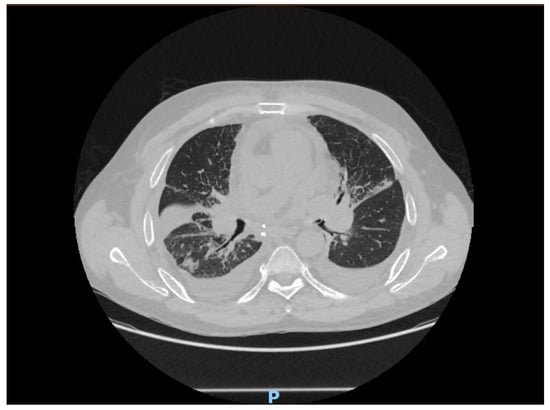

The computed tomography imaging showed bronchial congestion of the left upper lobar bronchia, with bilateral parenchymal condensations more marked at the level of the middle lobe and the right basal pyramid. Also, there were some areas of ground glass opacities with septal thickening, suggesting a possible infection (Figure 1).

Figure 1.

CT scan of the patient.